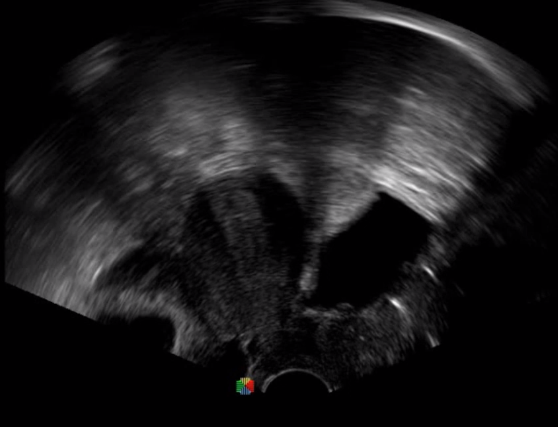

1生殖專用探頭

傳統(tǒng)腔內(nèi)探頭采用直柄設(shè)計,在搭配穿刺架使用時,手術(shù)空間小,不易操作;生殖專用的曲柄探頭,探頭柄采用彎曲成角度設(shè)計,可實(shí)現(xiàn)監(jiān)視、取卵兩不誤,搭載穿刺架時,可以清晰顯示穿刺針的進(jìn)針過程、深度和位置,實(shí)時監(jiān)視取卵全過程,保障取卵操作精準(zhǔn)與安全。

取卵臨床圖